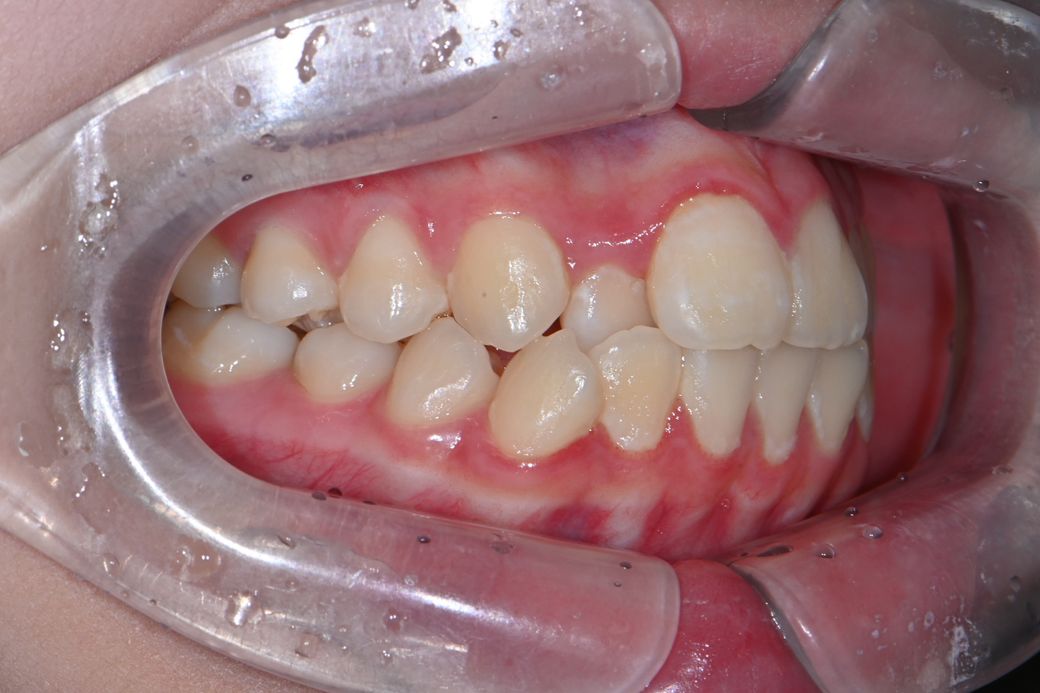

중1 여자 아이 교정진단 부탁드립니다.

앵글씨 몇급인지 궁금합니다.

의사 선생님마다 소견이 다르셔서 혼란 스럽네요.중1 여자 아이구요.시기적으로 지금 교정을 시작하기에 적절한지 궁금합니다.

• 1번 째 사진

앵글 2급 부정교합이며, 지금 교정하는 것이 좋을 것으로 보입니다. 더 늦어지면 교정이 까다로워 질 수도 있습니다. 지금 현재도 쉬운 케이스는 아닙니다.

앵글씨 부정교합측면에서 보면 1급인거 같고 치열이 좋지 않아서 중학교 1학년이면 교정을 시작하셔도 괜찮을 시기인거 같습니다.